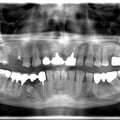

Руйнування зубів - результат тривалого користування бюгельними знімними протезами